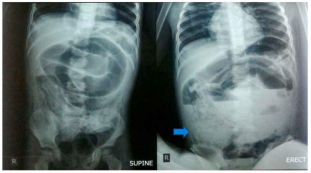

Paciente ABC, masculino, cinco anos, com história de queixa de dores abdominais, episódios de diarreia há pelo menos 15 dias. Há cerca de dois dias é admitido em um serviço de pronto-atendimento com queixa de piora da dor abdominal, constipação e anurese. Ao exame físico, a criança estava magra, com sinais e sintomas sugestivos de desnutrição. Na admissão, apresentava temperatura de 37,9°C, frequência respiratória de 22rpm e frequência cardíaca de 96bpm. Na anamnese, o paciente apresentava abdômen com contorno escuro no hipocôndrio direito, doloroso à pressão. A genitora nega investigação prévia de verminoses ou outras infecções intestinais ou uso de qualquer medicação. Foi realizado raio-X e evidenciada massa (Figura A) e o paciente foi encaminhado para laparotomia exploratória em que constataram-se múltiplas estruturas cilíndricas amarelo-esbranquiçadas, totalizando uma massa com peso de 540g (Figura B).

Figura A: Raio-X abdominal evidenciando alças dilatadas do intestino delgado.